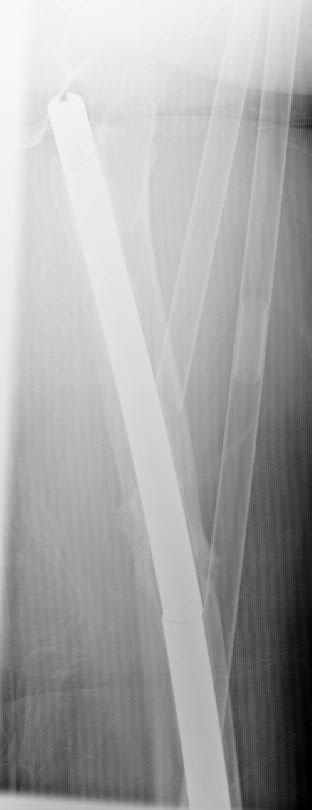

May I have some advice on the following case? Middle aged woman, No chronic medical problems, +tobacco use - but she promises she's going to quit! Original MVC in late 1990's, initial rod failed, and 2 subsequent exchanges failed (most recently shown in attached jpgs.)

Most recent one (6/2002) was apparently an open nailing to remove last broken nail, but no grafting was performed in conjunction. Now sent to me with broken 14mm R/T nail in place. WBC, Hgb, Chemistries normal. ESR 34 CRP 4.2 No other apparent locus of infection. I was considering a staged approach - removing nail and screws and obtaining cultures. If negative, proceed with exchange nailing with open grafting +/- BMP, But how best to deal with that pedestal distally and avoid anterior breech near patella? If positive cultures, what would be best option? Thanks. Tom Schaller Kalamazoo, MI.